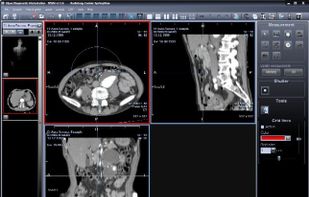

The Hipax Diagnostic Workstation is a new generation of Hipax viewer software, developed specially to cope with very big image series. The new viewer concept allows an optimal workflow.

The Hipax Diagnostic Workstation is a new generation of Hipax viewer software, developed specially to cope with very big image series. The new viewer concept allows an optimal workflow.

The images can already be processed while the series are still loaded – the loading process is carried out in the background, unnoticed by the user and without loss of performance. The different image processing functions can be used in maximum speed even on very big image series. The multiplanar reconstruction opens additional possibilities for radiologists to evaluate images.